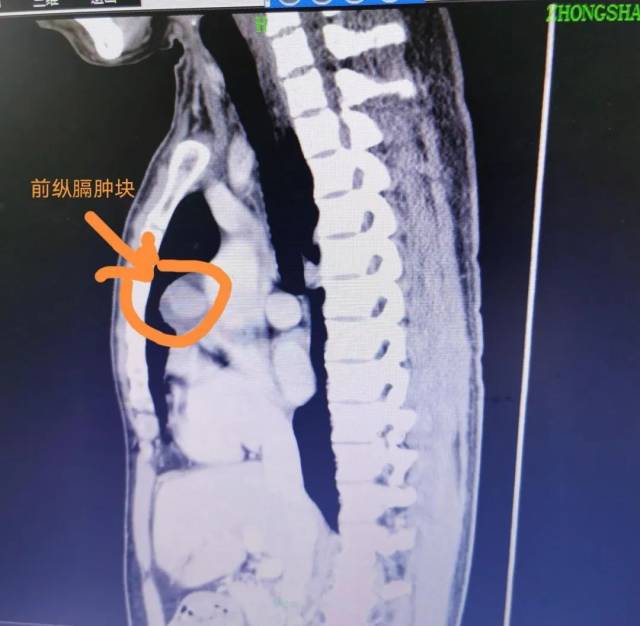

随后 , 他来到中山某医院就诊 , 经过胸部CT检查发现 , 胸部前纵隔有鸡蛋大小的肿瘤 , 而且紧靠心脏 , 挤压非常重要的大血管 。

根据陈先生的症状表现及影像结果 , 胸外科医生考虑存在胸腺瘤的可能 。

经过约1个半小时的微创手术操作 , 成功摘除前纵隔肿瘤 , 并清扫前纵隔脂肪组织 。 幸运的是 , 经过病理切片组织标本送检结果显示 , 陈先生前纵隔肿瘤为良性胸腺瘤 。